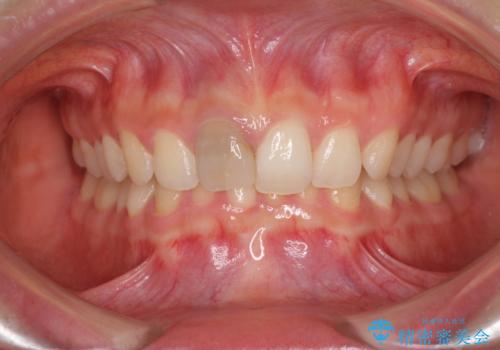

- 中学生の時にぶつけて神経を取り除いた前歯の変色が気になるとのことで来院された患者様です。

レントゲン写真より、歯根の炎症が認められなかったため、ファイバーコアによる土台築製後、オーダーメイドタイプのオールセラミッククラウンにて補綴することとしました。